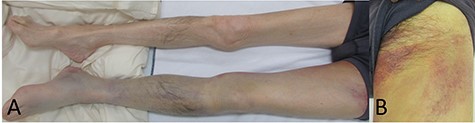

The patient looked pale but was conscious. He was thin and weighed 40 kg (body mass index, 14.5) due to loss of appetite after gastric surgery; however, his left thigh was reddish, edematous and painful (Fig. 1). Hemodynamics, such as blood pressure and heart rate, were stable. Blood tests revealed a hemoglobin level of 3.41 mmol/l. Ultrasonography showed a 72 × 52 mm PFAA with a thick thrombus and hematoma extending into the adductors (Fig. 2). A venous thrombus was also observed in the left femoral vein. Enhanced computed tomography (CT) revealed a ruptured left PFAA 64 × 54 mm in diameter (Fig. 3A and C). In addition, right iliac artery aneurysm and right CFA and SFA occlusion were also observed.

(A) Picture of the lower extremities of the patient. His left limb was edematous and hemostatic. (B) Picture of the left thigh. The patient’s thigh appeared reddish and had pain.